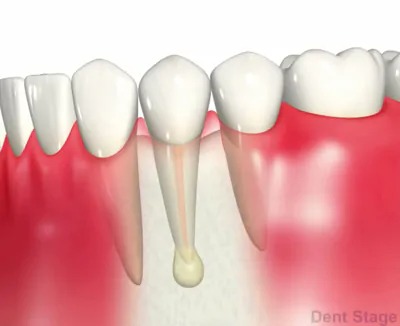

むし歯が進行して神経にまで達すると、「冷たいものや甘いものがしみる」「温かいものでズキッと痛む」「噛むと痛い」などの症状が現れることがあります。さらに悪化すると、何もしていなくてもズキズキと痛みが出たり、歯ぐきが腫れたりすることもあります。このような状態になると、神経を取り除く「抜髄」や、すでに神経の治療をした歯に再び炎症が起きた場合は「再根管治療」が必要になることがあります。また、痛みが出ないまま進行しているケースもあるため、レントゲンなどでの定期的なチェックが大切です。

むし歯を繰り返すと、最終的には神経を取って「根管治療(歯の根の治療)」を行う必要が出てきます。根管治療が適切に行われれば、ご自身の歯を残すことができます。しかし、治療の際に細菌が残ってしまうと、根の先に膿がたまり、再治療が必要になる場合があります。

歯根端切除術

根管治療を行なっても症状が改善しない場合や根尖病巣が大きすぎて、根管治療では治せない場合等で行う施術方法です。歯茎を開いて、外科的な明視野で直接根尖病巣(歯根のう胞、歯根肉芽種)を取り除き、症状の改善を図ります。(※第一大臼歯までが適応です)